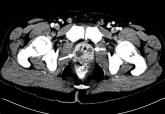

ArticleMethicillin‐resistant Staphylococcus aureus bacteremia due to prostatic abscessAuthor:Jason M. Kidd, BSPublish date: January 12, 2009Read More